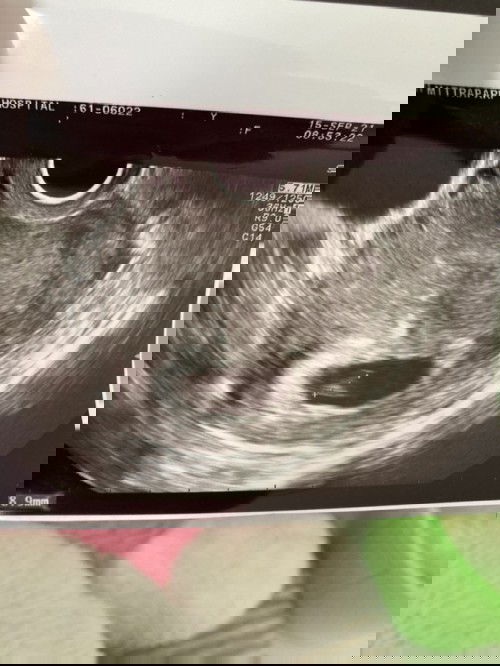

คือว่ามีภาวะมีบุตรยากค่ะ แต่งงานมา6ปี ปัจจุบันอายุ35จะ36อีกไม่กี่เดือน😁 เราถึงขั้นที่ไปพบหมอเพื่อปรึกษาการทำอิกซี่ เข้าสู่ขั้นตอนแล้วคือตรวจร่างกายทั้งเราและสามี ได้ยาบำรุงมาทานทั้งคู่ ผลปรากฏว่า เดือนถัดมาประจำเดือนขาดค่ะ เป็นคนจำแม่นอยู่แล้วเพราะใจจดใจจ่อกับประจำเดือนมาตลอด ใช้ที่ตรวจตรวจขึ้นสองขีดชัดมากค่ะ แต่ยังงงๆอยู่ว่ามันใช่ไหม เพื่อความแน่ใจไปโรงพยาบาลค่ะ ผลออกมาท้องจริงๆค่ะ เหมือนปฏิหาริย์ค่ะสำหรับเรา อัลตร้าซาวผ่านช่องคลอดไม่เจอ แต่คุณหมอก็บอกว่าไม่แปลกเพราะครรภ์ยังอ่อนมาก นับจากประจำเดือนคือเกือบ5สัปดาห์ นัดอีกที2สัปดาห์ค่ะ(7w) ปรากฎว่าก็ยังไม่เจอค่ะ คุณหมอบอกเป็นนัยๆให้เราทำใจว่าอาจเป็นท้องลม เศร้าเลยค่ะ😔 คุณหมอขอตามอีก2สัปดาห์ค่ะ(9w) ผลปรากฏว่าเจอค่ะ เย้ๆ แต่คุณหมอบอกว่าไม่ได้ยินเสียงหัวใจอาจเพราะยังเล็กมากค่ะ ในเครื่องอัลตร้าซาวบอกผลว่า6สัปดาห์ค่ะ(ตามขนาด8mmค่ะ) วันนั้นก็ฝากครรภ์เลยค่ะเจาะเลือดชุดใหญ่😁 แล้วหมอนัดอีกที3สัปดาห์ค่ะ อ่อเรามีเลือดออกด้วยนะคะแต่ไม่มากเป็นสีน้ำตาลค่ะ (ไม่ออกทุกวันนะ )ได้ฉีดยากันแท้งไปทั้งหมด2เข็ม ผ่านไป2สัปดาห์มีเลือดออกมาอีก1ครั้งค่ะแต่ออกมาแค่นั้นไม่ออกตลอด ถัดมาอีก3วัน(11w3d)(คือวันนี้)มีตกขาวสีน้ำตาลจางๆออกมา เลยไปหาหมอค่ะ ผลอัลตราซาวด์ออกมาคือ น้องไม่โตค่ะขนาดเท่าเดิมคือ8mmค่ะ ไม่พบหัวใจ😭 (เราไม่มีอาการปวดท้องเลยค่ะ) สุดท้ายขูดมดลูกค่ะ พรุ่งนี้หมอนัดขึ้นเขียงค่ะ คุณหมอให้กำลังใจเราดีมากทั้งๆที่อายุเราจะ36แล้ว หมอบอกสบายมากค่ะไม่ใช่ปัญหา เราก็ใจฟูขึ้นมาเลยค่ะ น้องไม่พร้อมเราบังคับน้องไม่ได้😔 เป็นกำลังใจให้แม่ๆทุกท่านไม่ว่าจะด้วยวิกฤตอะไรขอให้แม่ทุกท่านเข้มแข็งนะคะ💕